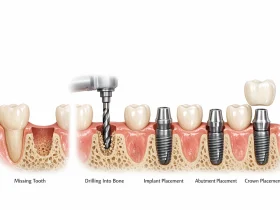

ایمپلنت دندان به عنوان یکی از روشهای مهم و مؤثر برای ترمیم جای خالی دندان شناخته میشود. این ...

ایمپلنت دندان یکی از ماندگارترین راهکارها برای جایگزینی دندان از دست رفته است و بسیاری از بیماران ...

چرا جایگزینی دندانهای از دست رفته اهمیت دارد؟از دست دادن دندان تنها یک مشکل ظاهری نیست و ...